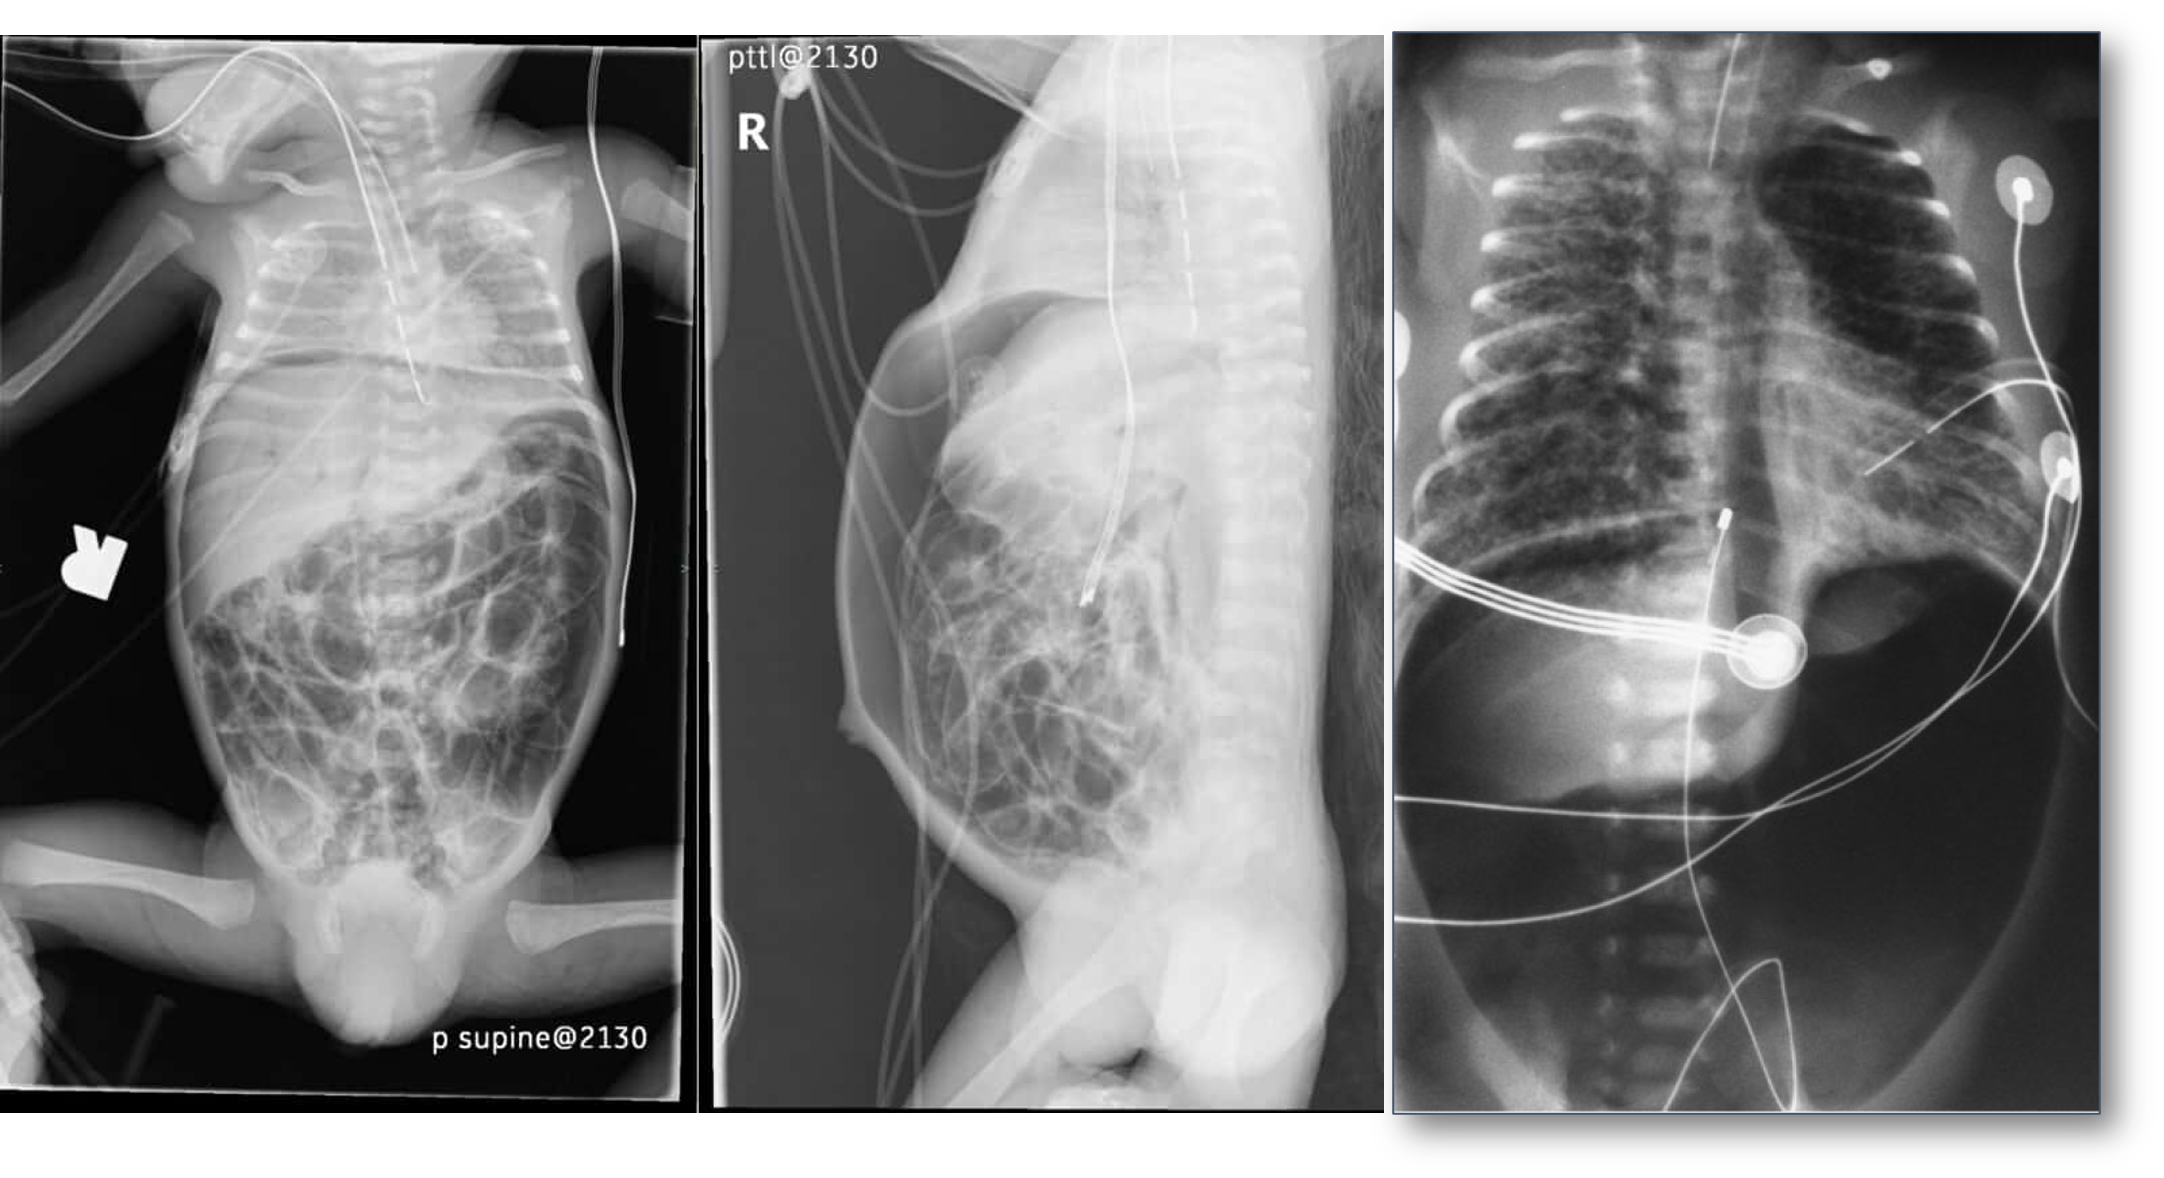

Case 4

A preterm infant born at 25 weeks gestation is now 6 weeks old. The infant has been stable for the past few weeks, breathing in room air, and receiving full enteral feedings that consist of fortified maternal breast milk and some formula supplementation. Yesterday, the infant had a few large gastric residuals with feeding but was otherwise well. Today, you were called for a new onset of apneic spells, increased abdominal distension, poor urine output, lethargy, and hypothermia.

What is your spot diagnosis? necrotizing enterocolitis

- Dilated loops,

- thickened bowel walls,

- pneumatosis intestinalis (air in intestinal walls),

- pneumoperitoneum; indicate perforation (emergency requiring surgical intervention),

- portal gas (present in the portal venous system,

- considered to be a poor prognostic sign).

Further Deterioration

Despite your treatment, the patient deteriorated and was admitted to the NICU.

- What is your action? immediate surgery

inflamed, necrosis ⇒ Perforation everywhere

dark circles air in intestinal wall

Air in portal gas

Pneumoperitoneum

- Notice:

Pneumoperitoneum. - due perforations